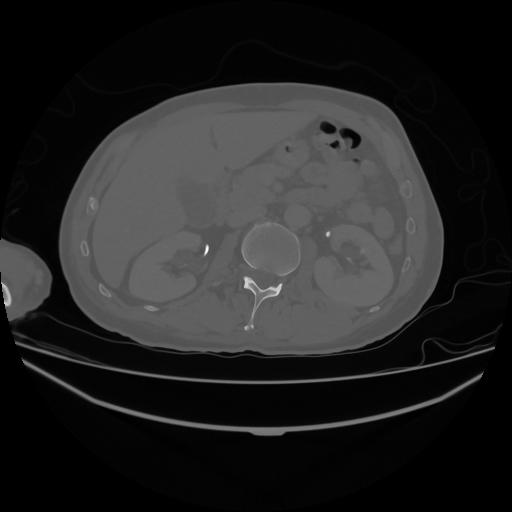

5 CUERPO,CE,Vol,1.0,CUERPO,,